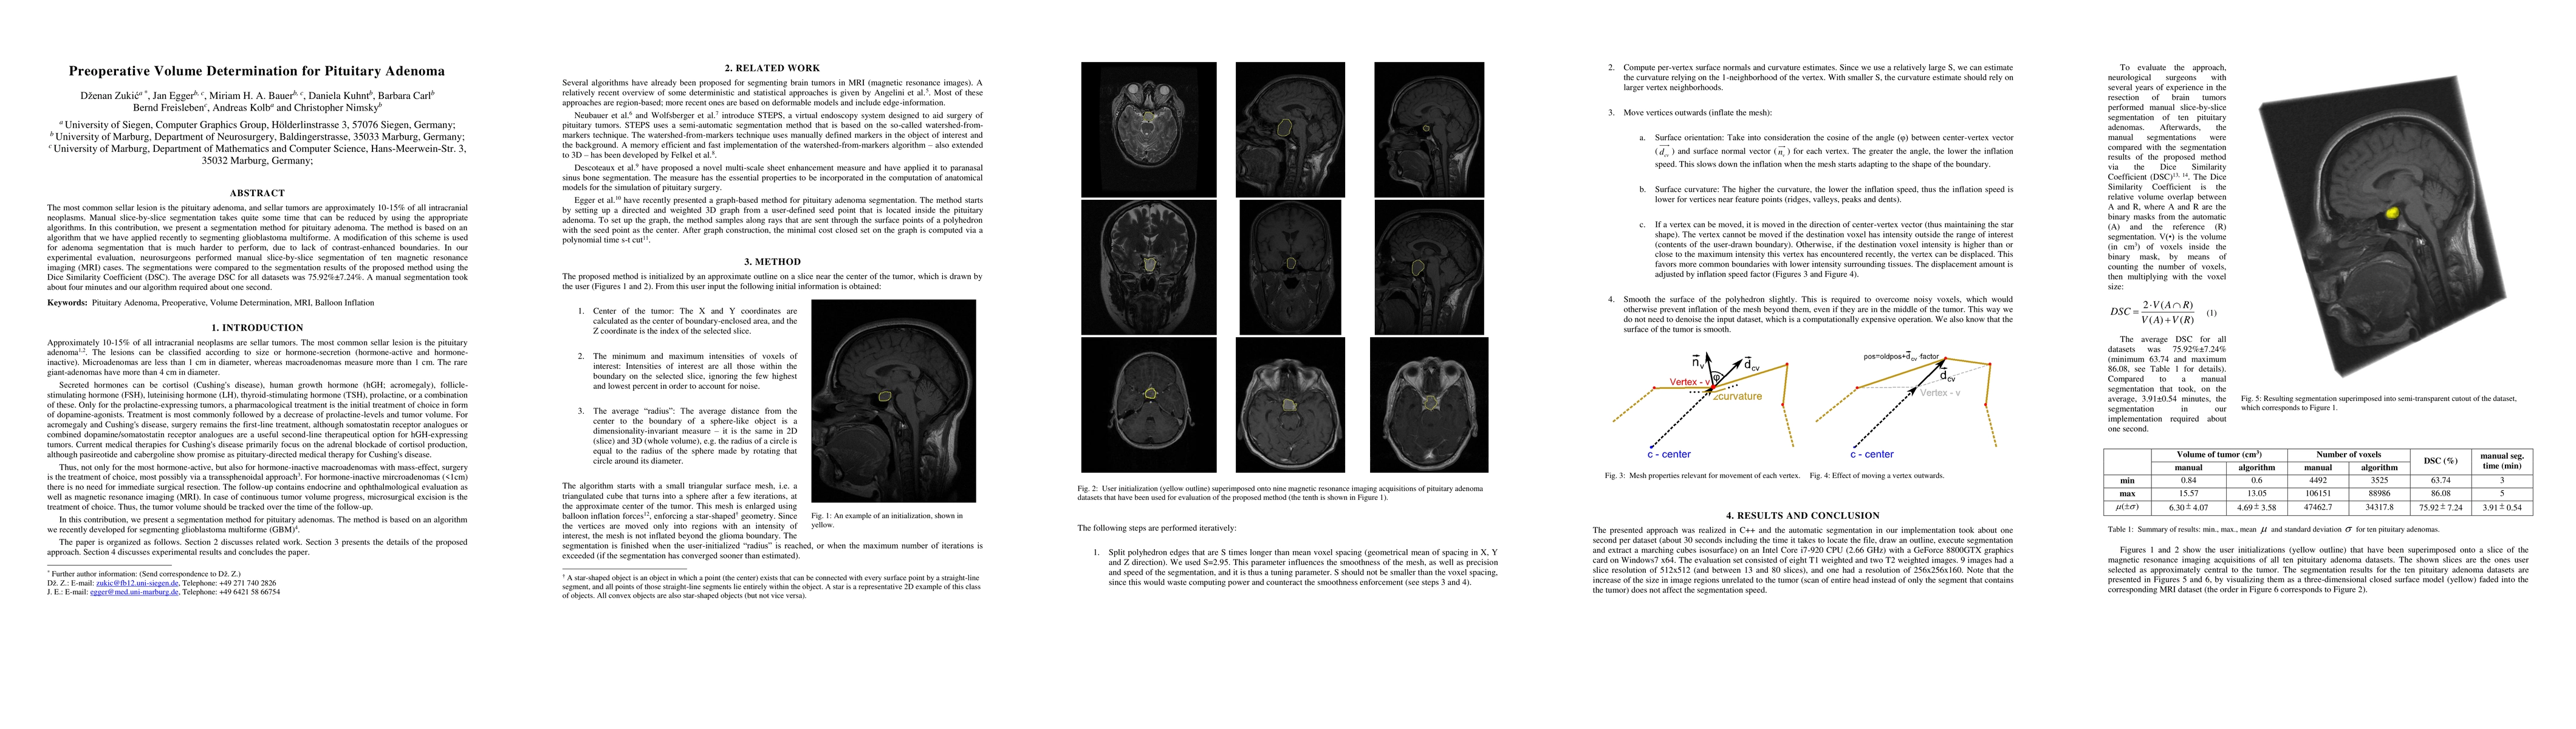

The most common sellar lesion is the pituitary adenoma, and sellar tumors are approximately 10-15% of all intracranial neoplasms. Manual slice-by-slice segmentation takes quite some time that can be reduced by using the appropriate algorithms. In this contribution, we present a segmentation method for pituitary adenoma. The method is based on an algorithm that we have applied recently to segmenting glioblastoma multiforme. A modification of this scheme is used for adenoma segmentation that is much harder to perform, due to lack of contrast-enhanced boundaries. In our experimental evaluation, neurosurgeons performed manual slice-by-slice segmentation of ten magnetic resonance imaging (MRI) cases. The segmentations were compared to the segmentation results of the proposed method using the Dice Similarity Coefficient (DSC). The average DSC for all datasets was 75.92% +/- 7.24%. A manual segmentation took about four minutes and our algorithm required about one second.